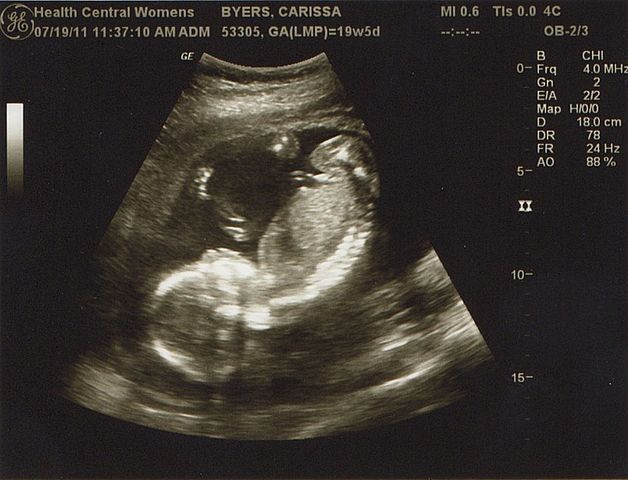

• primer ecografia

primer ecografia

la primera ecografia fue relizada en el quinto mes de gestación en la cual el feto no dejo ver que sexo era pero la doctora señalo que el bebe estaba en perfecto estado